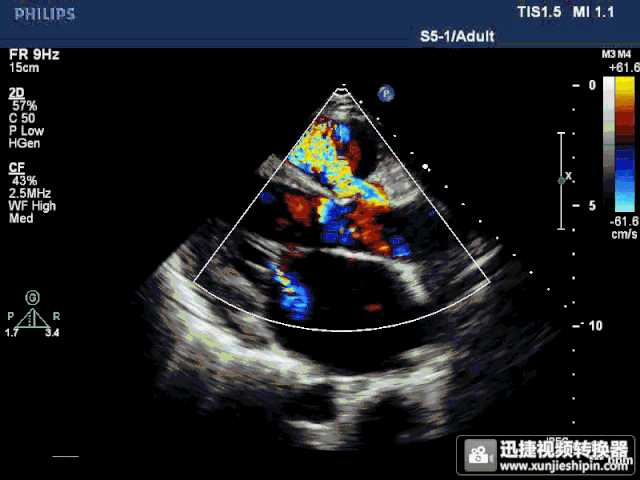

rvot 右室流出道 cs 冠状静脉窦)1, 左位上腔静脉;2, 左心房扩大超声

e,左冠瓣脱垂 超声示:右室流出道切面显示右冠状动脉窦呈袋状扩张

房室瓣后方水平:与左心室二尖瓣环后方相平行的间隙为冠状静脉窦